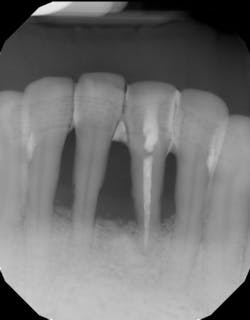

- Ensure tooth does not have a root fracture and check/refer for endodontic treatment if tooth is nonvital (figure 1)

- Proper surgical technique including incision, flap design, and complete detoxification of bony defect and root apices (figures 3 and 3a)